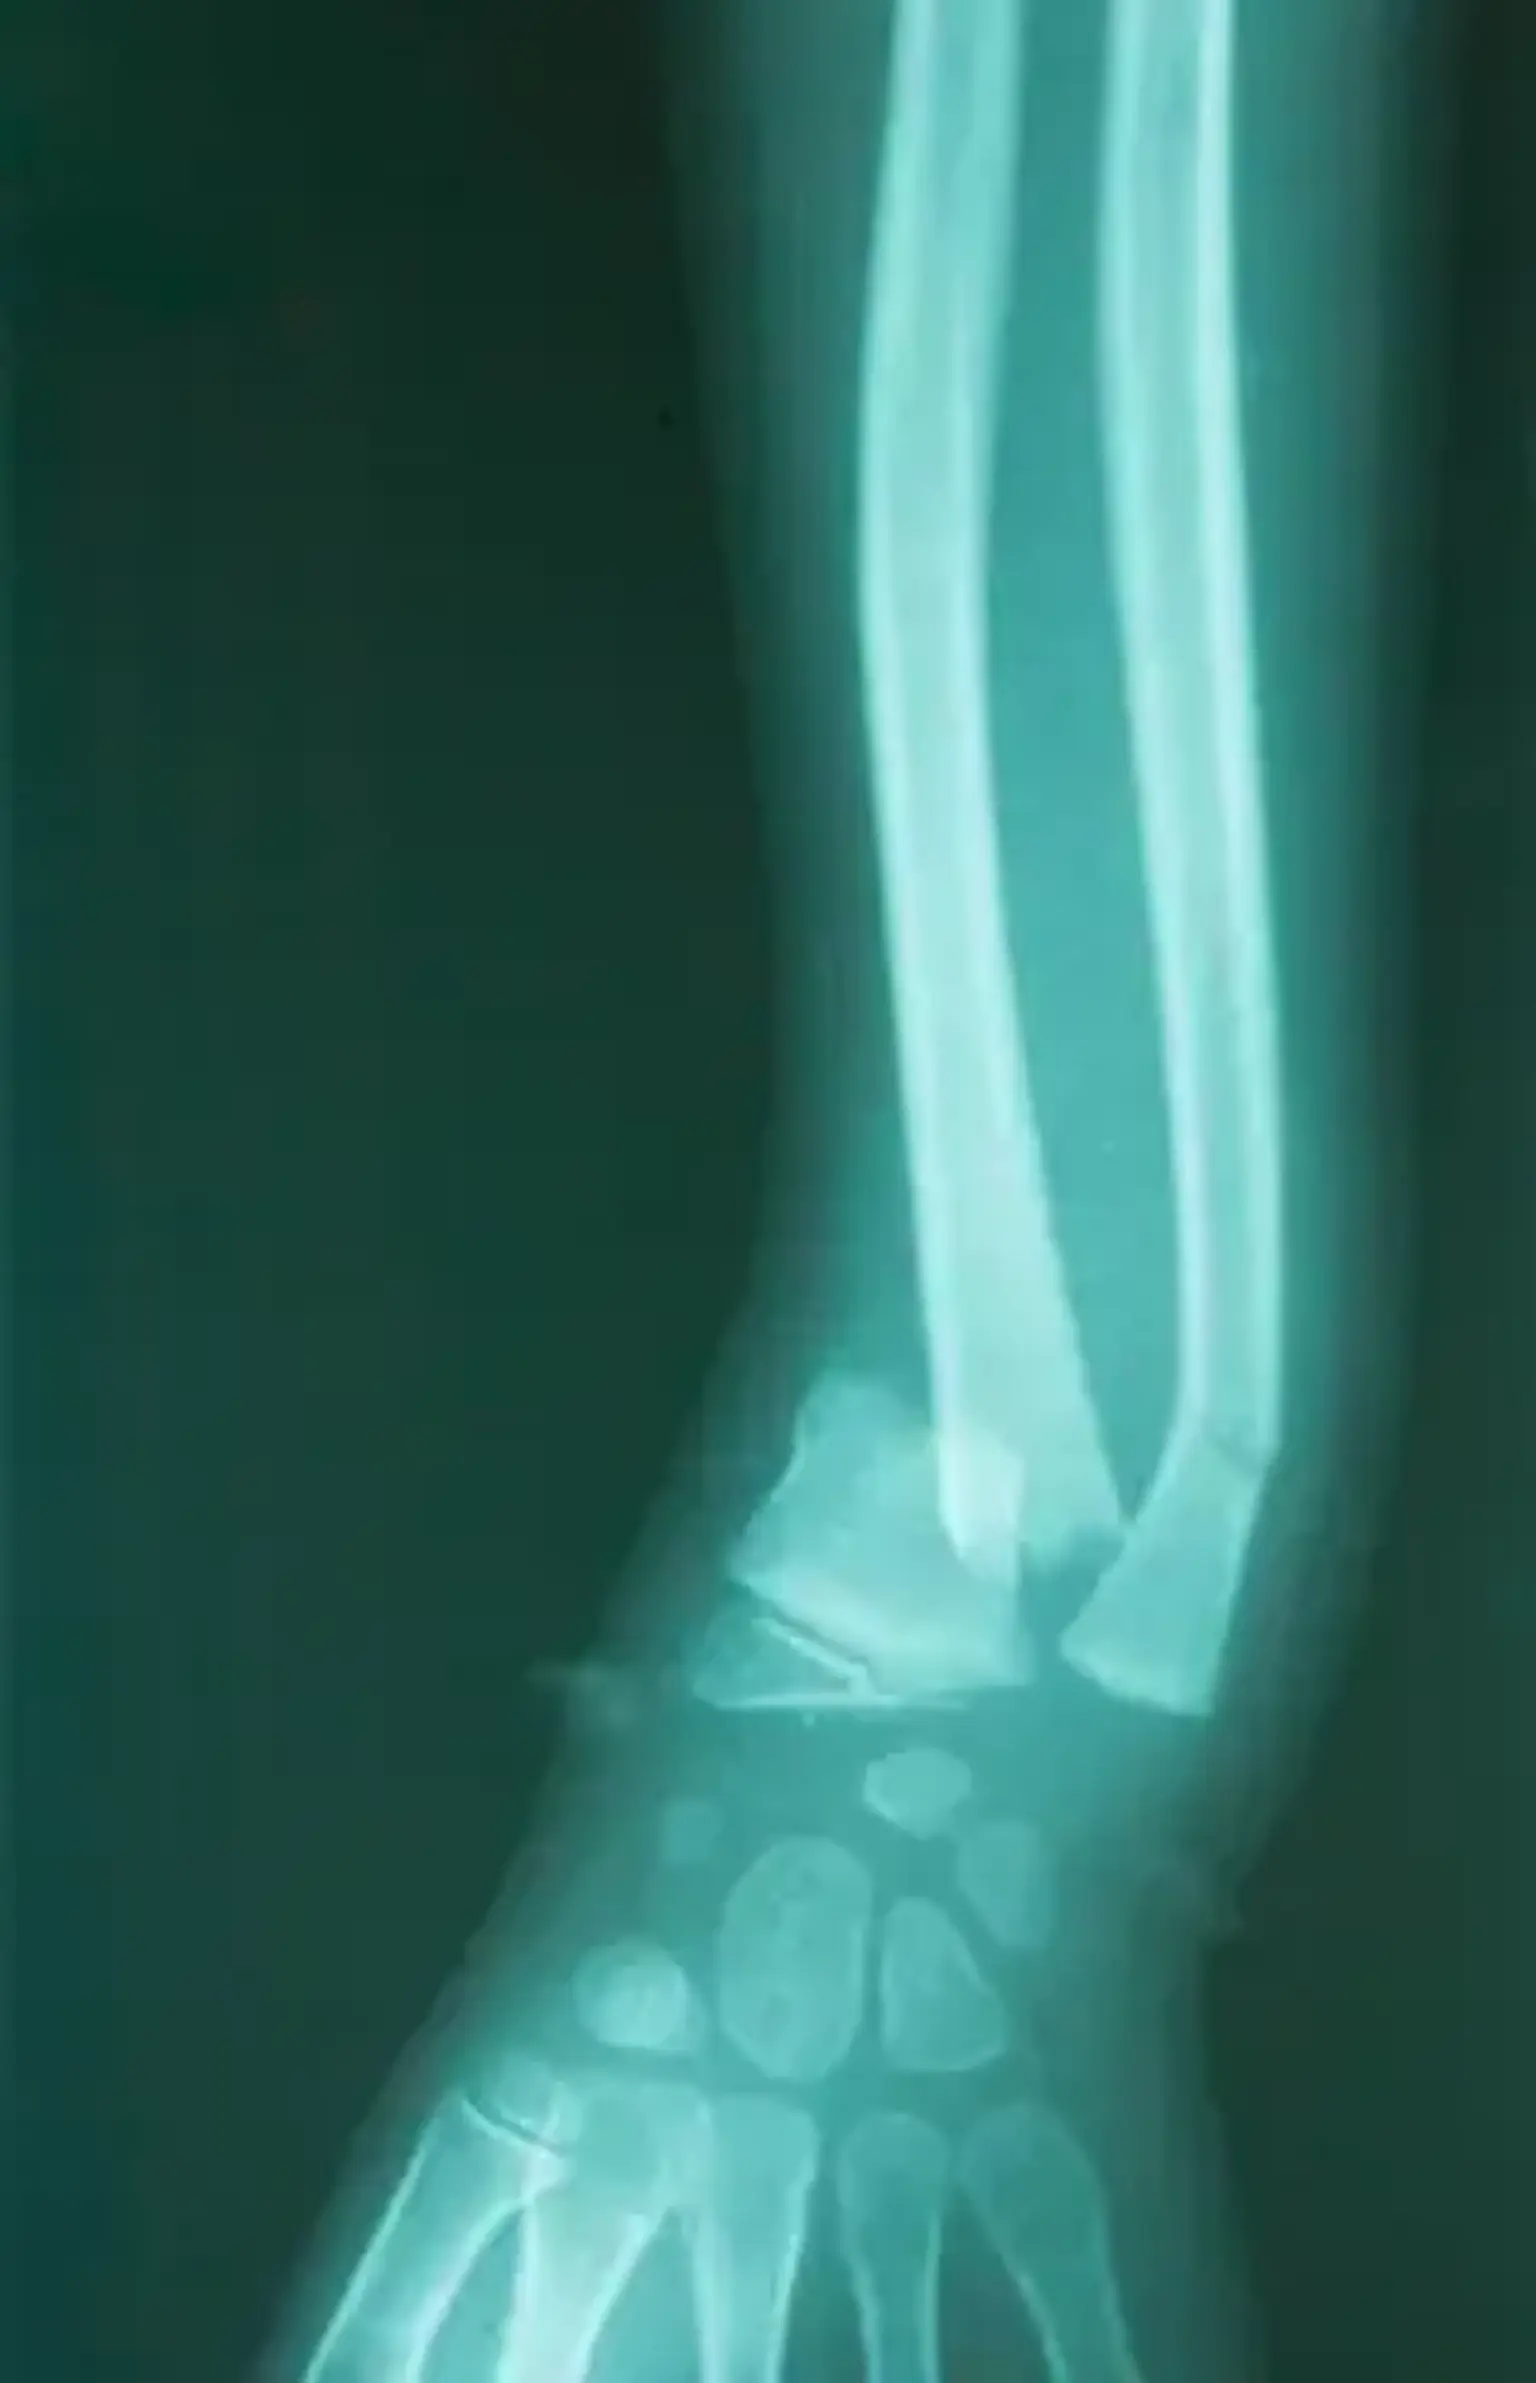

Pediatric Fracture Diagnosis: How Doctors Identify Bone Breaks in Children

When a child sustains a possible bone fracture, an orthopedic specialist will conduct a physical examination to assess pain, swelling, and the ability to move the affected limb. X-rays are the most common diagnostic tool used to confirm fractures and determine the type and severity. In some cases, MRI or CT scans may be used for more complex fractures or those near growth plates.